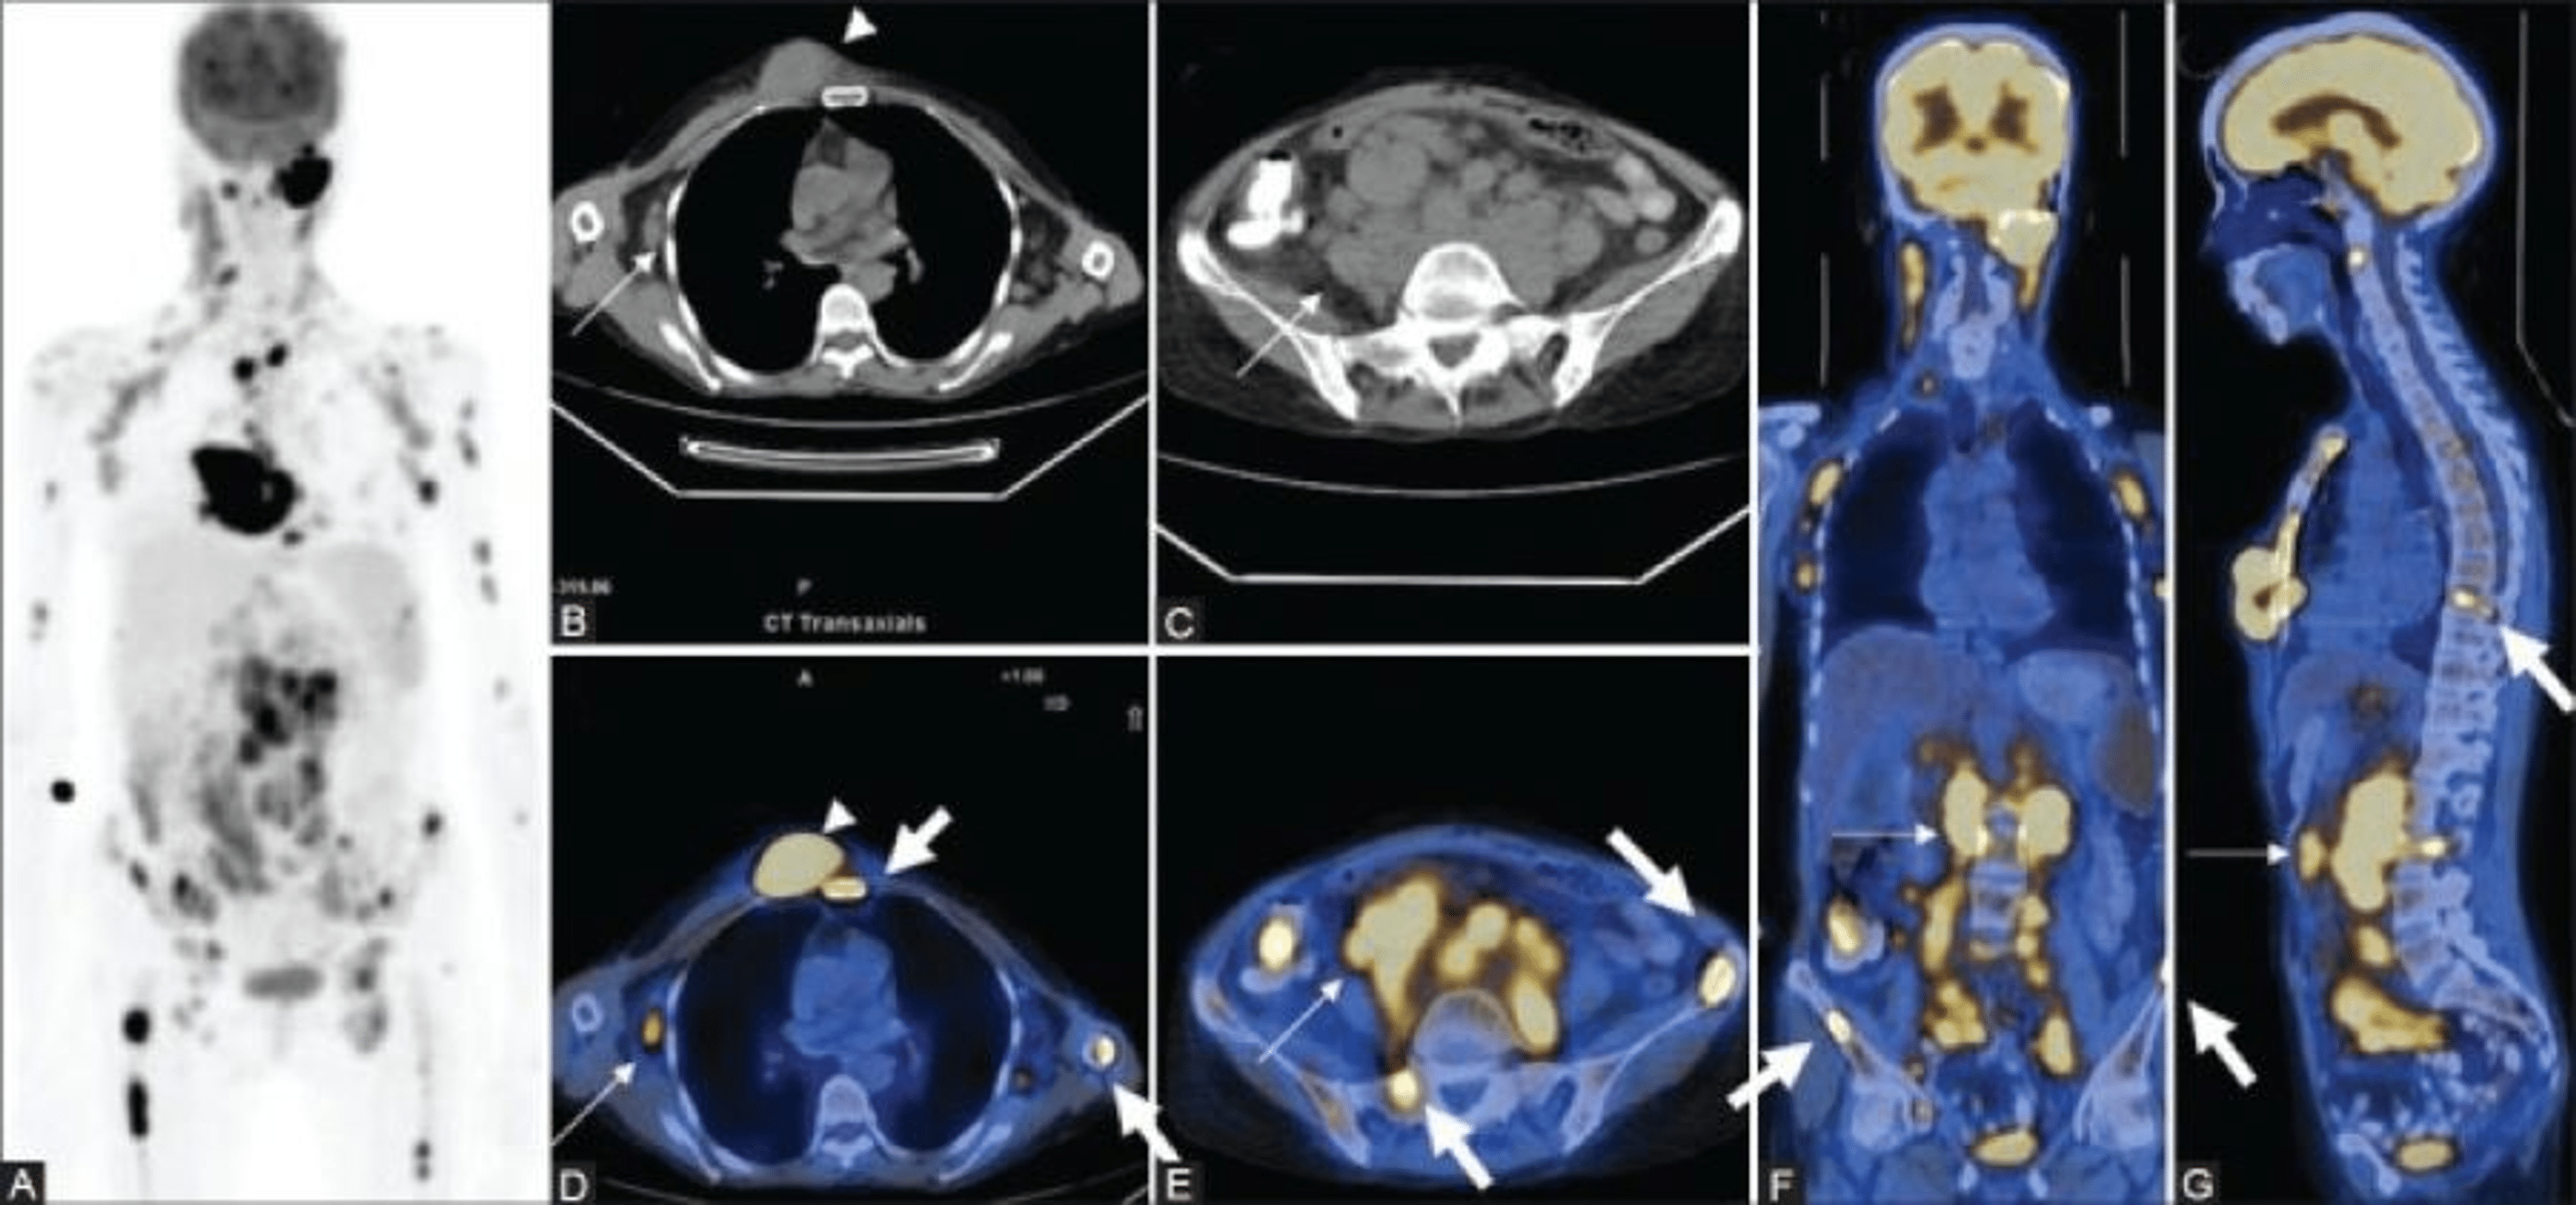

From www.cureus.com

Cureus Changing Role of PET/CT in Cancer Care With a Focus on Radiotherapy Can Esr Detect Lymphoma complete blood count (cbc) is the most common blood test performed for people with lymphoma. hodgkin lymphoma, once known as hodgkin disease, is a group of blood cancers that usually develops in your lymphatic. A higher than normal value may. a test called an erythrocyte sedimentation rate (esr) can help measure how much inflammation is in the. Can Esr Detect Lymphoma.